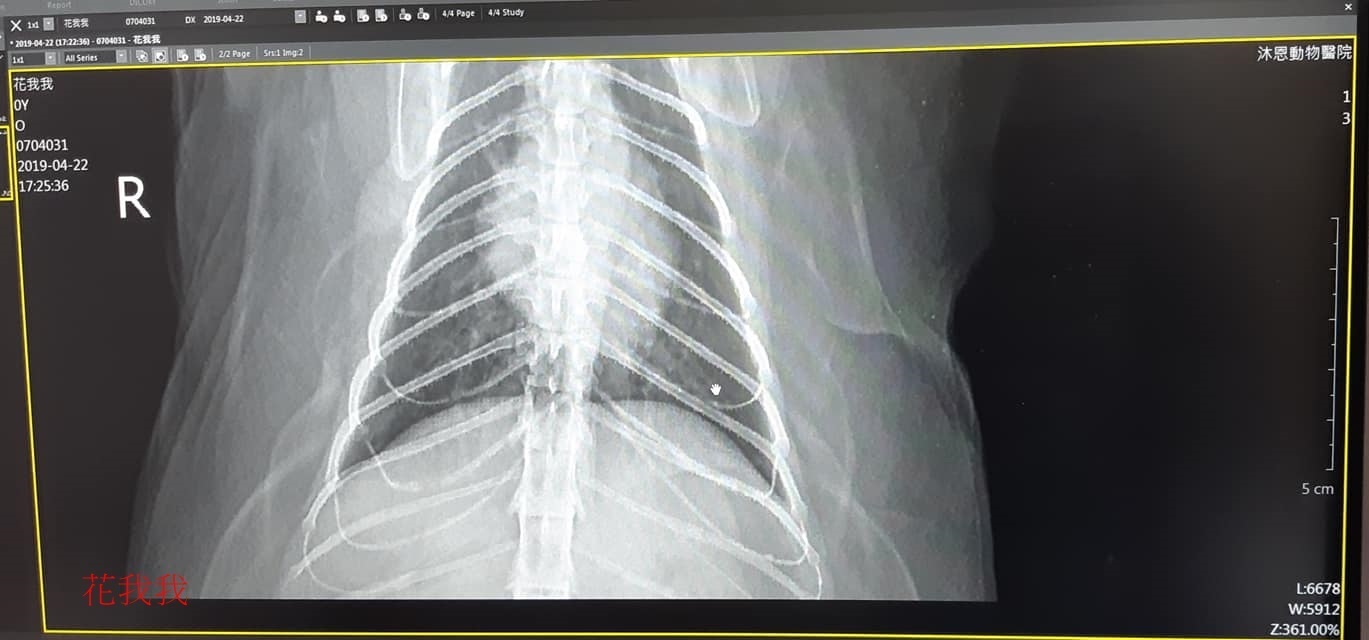

4月時照護員看到花我我咳嗽不停,錄影片及約診沐恩醫院,醫師從X光中發現支氣管有些鈣化,因此研判是支氣管發炎,開一週口服藥並囑咐多觀察。

本筆醫助為花我我在4月22日於沐恩看診的費用,希望大家可以一起幫忙,謝謝。

4/22 花我我 沐恩看診 楊醫師

體重:4.990kg

一、看診情形

沒有做血檢,今日觸診及拍x光,從X光看來肺部發現沒有異常,但有看到支氣管的影像,楊醫師說明,X光應是看不到支氣管,通常是貓咪年紀大時,支氣管有些鈣化才會看到,花我我年紀尚輕,因此研判是支氣管發炎,先開藥服用一週看有無改善。

二、用藥

1. 胃藥:飯前,早晚各1顆。

2. 抗生素:飯後,早晚各1顆。